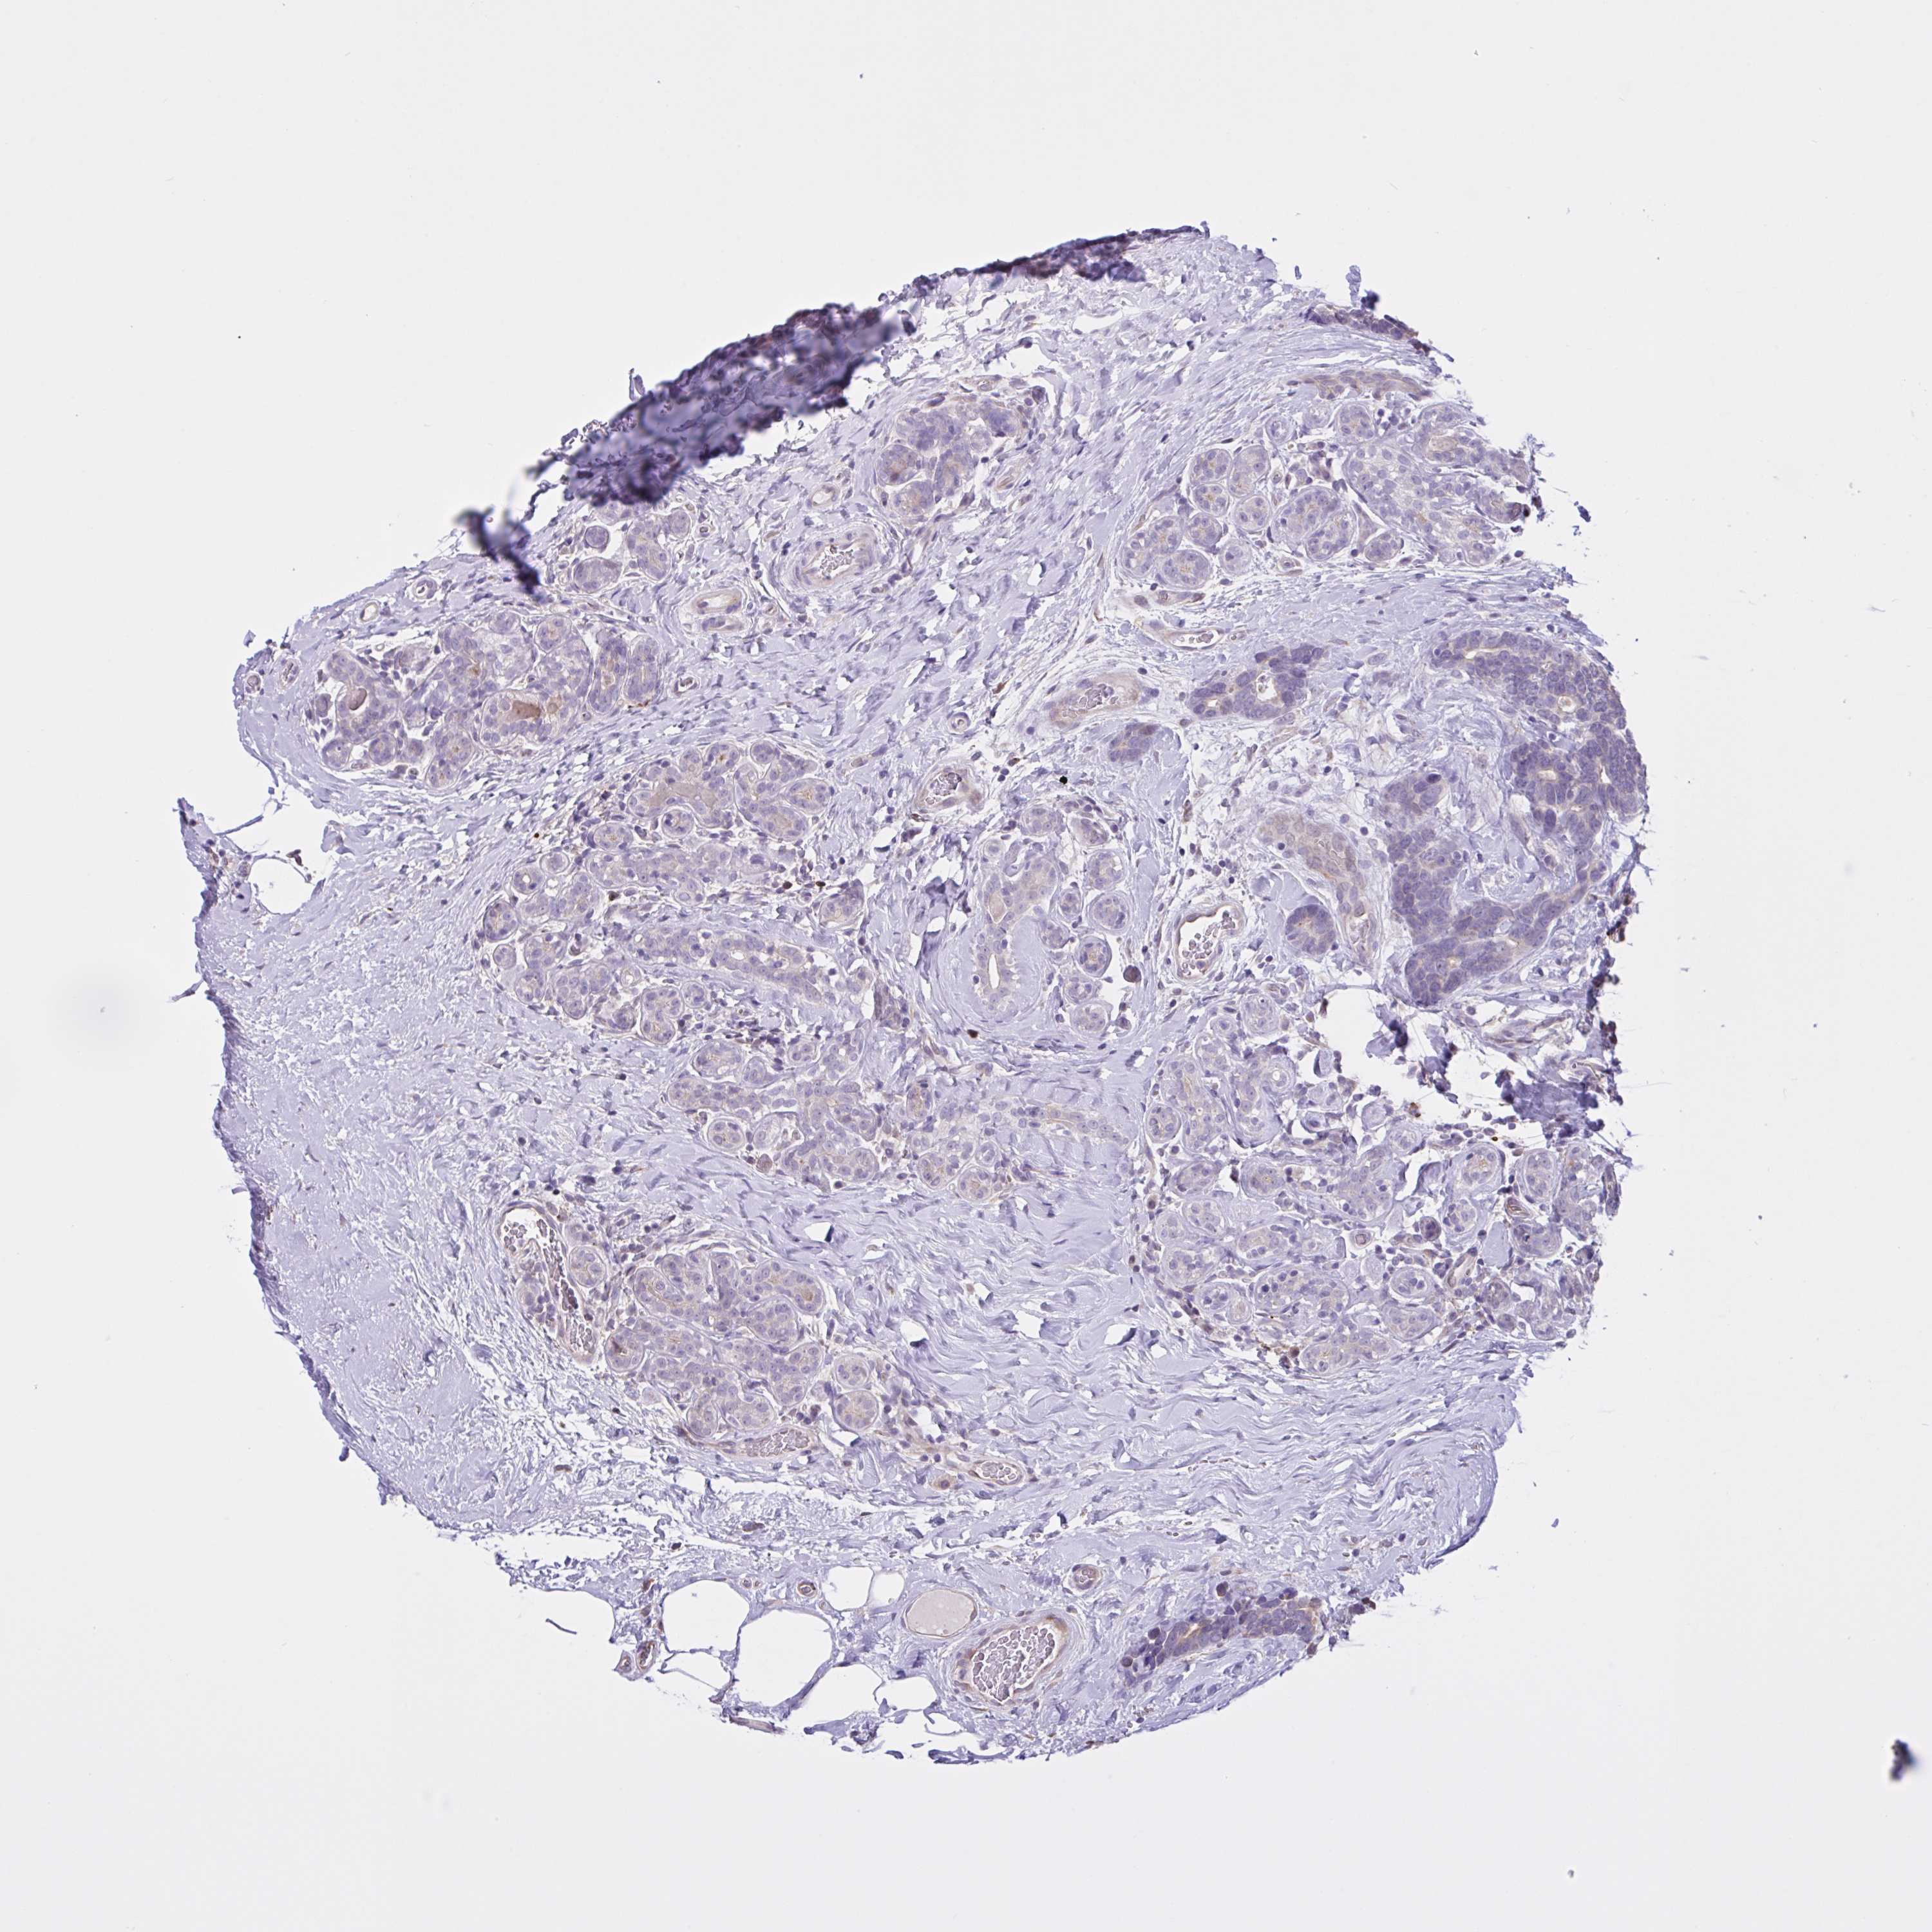

CANCER BREAST CANCER Show tissue menu

BRCA TCGA BRCA VALIDATION PROTEIN EXPRESSION